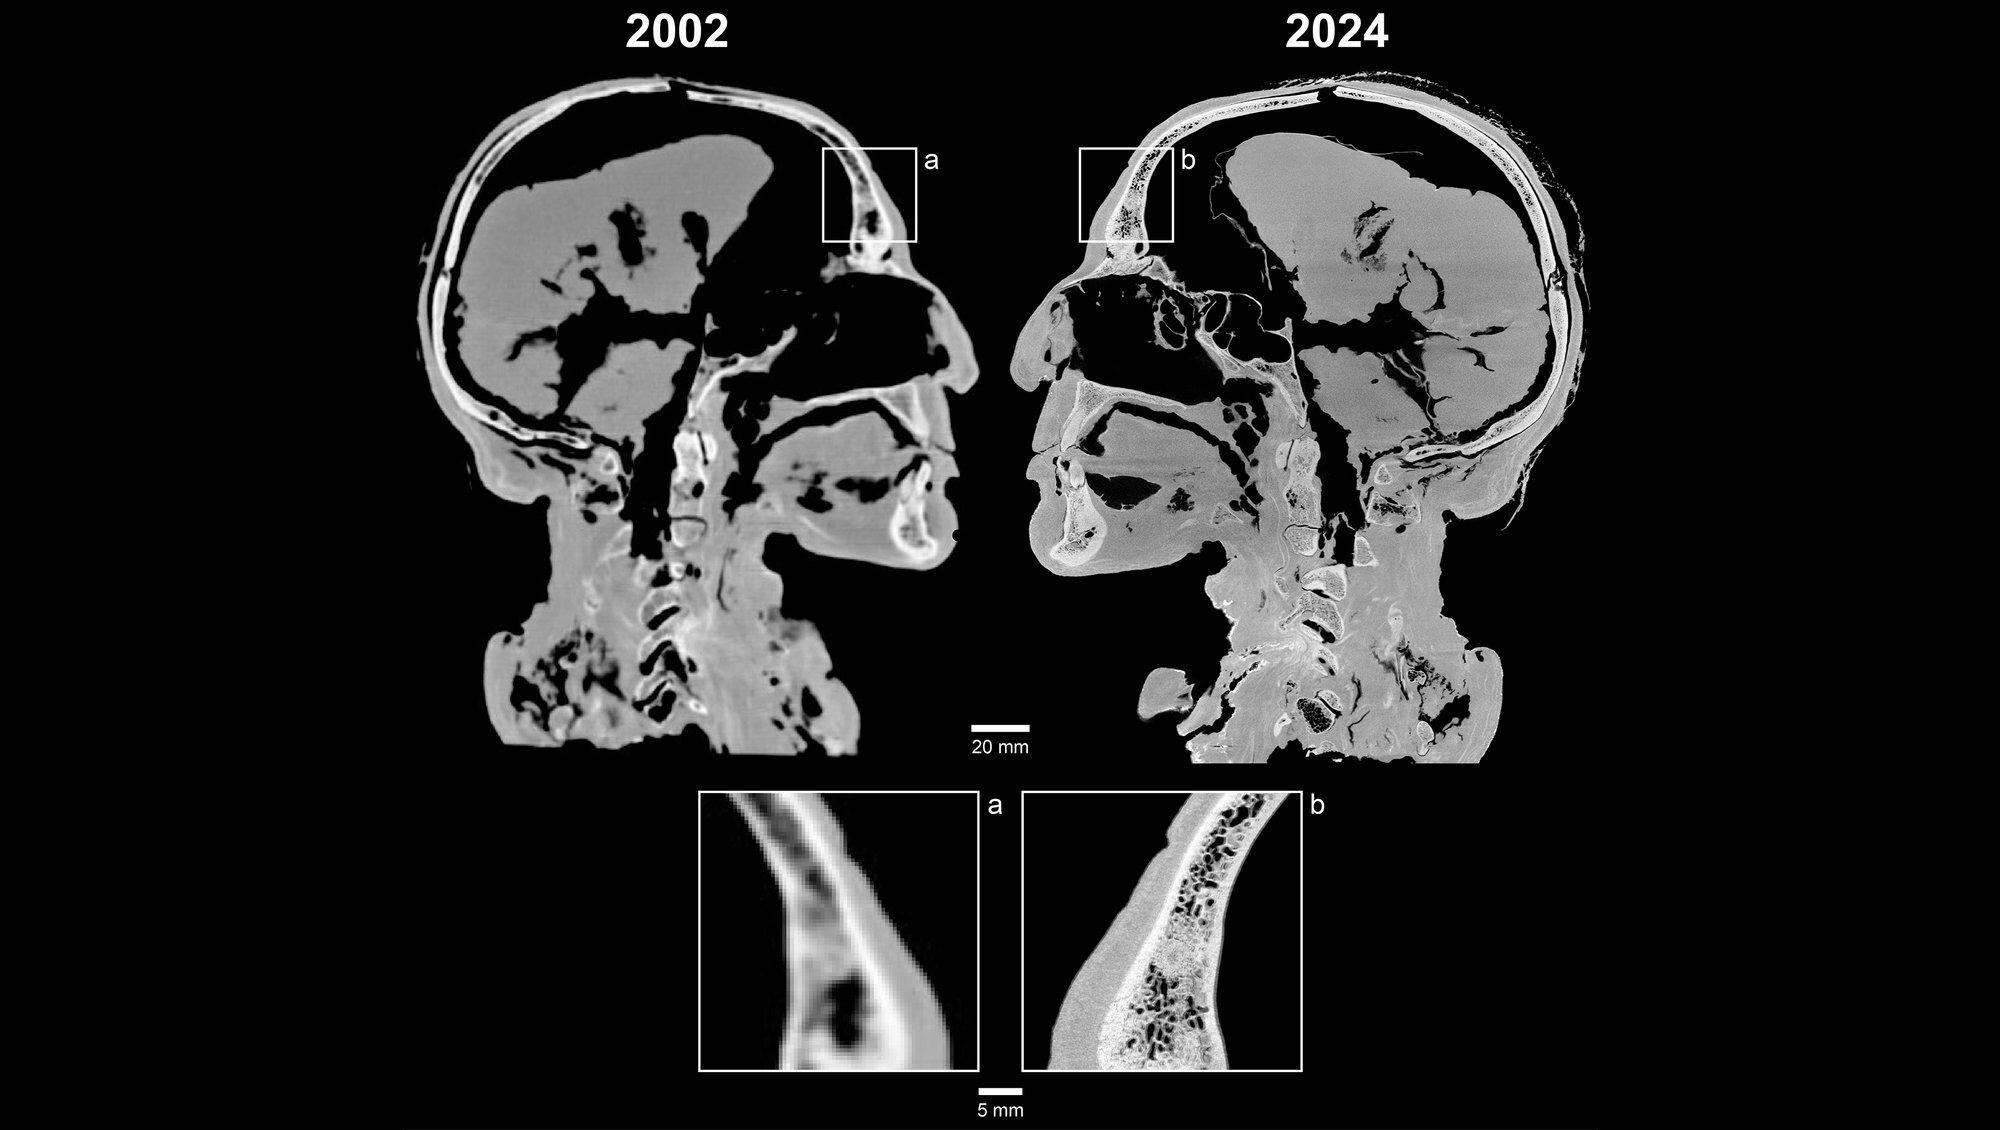

In a recent secretive collaboration between Aarhus University and Museum Silkeborg, Tollund Man's head underwent a micro-CT scan using a TESCAN CoreTOM system. This state-of-the-art technology offers up to 4000 times higher resolution compared to previous scans.

Virtual autopsy of Tollundman's head and brain. With digital dissection, the brain can be viewed - it is well preserved.